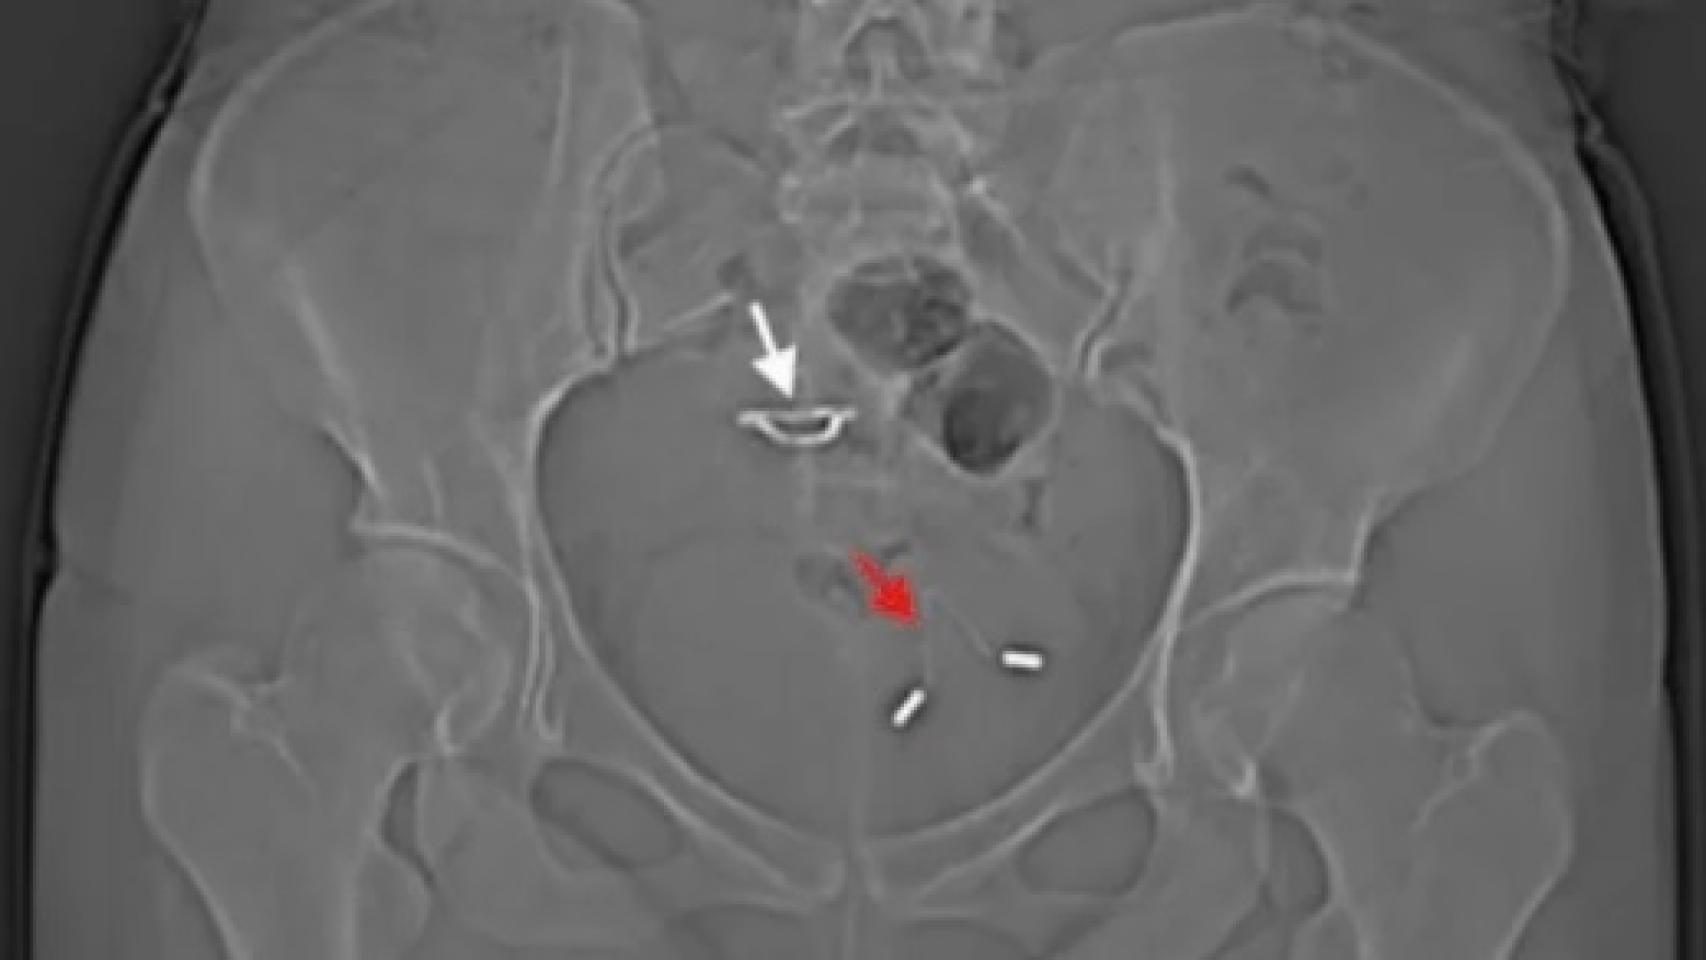

La verdadera explicación al suceso llegó cinco años después, cuando la paciente acudió a los servicios de urgencias aquejada de dolor abdominal, frecuencia excesiva en la micción y restos de sangre en la orina. Al hacer una radiografía de su pelvis, los sanitarios descubrieron que aquel DIU perdido había salido del útero y había acabado en la vejiga, dónde había comenzado a causar problemas crónicos.

La causa debió ser un fenómeno real, pero muy poco frecuente, que tiene lugar cuando el dispositivo perfora las paredes del útero y se aloja en algún lugar del abdomen. En este caso también había perforado la vagina, causando una lesión que se había curado por sí sola, pero dejando secuelas a su paso. Ya en 2016 se documentó un caso similar en Grecia y, de hecho, se han notificado unos 40 más en los últimos 10 años, producidos por causas muy distintas.